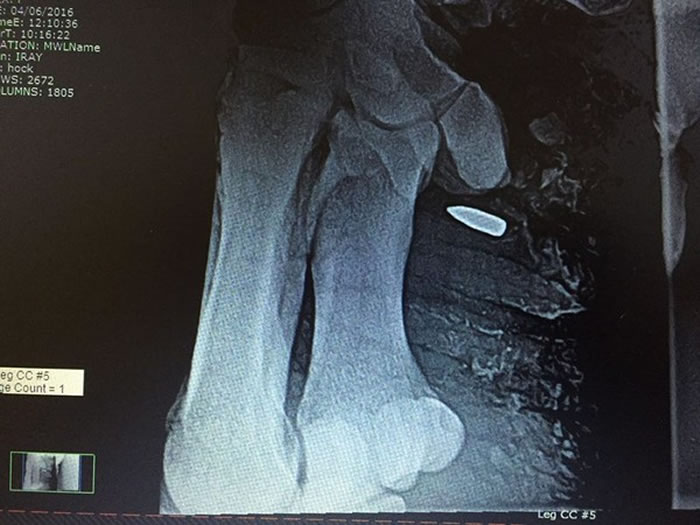

兽医为犀牛妈妈照X光确认伤势

子弹深入犀牛的脚

它在盗猎者的追击中被子弹打中脚